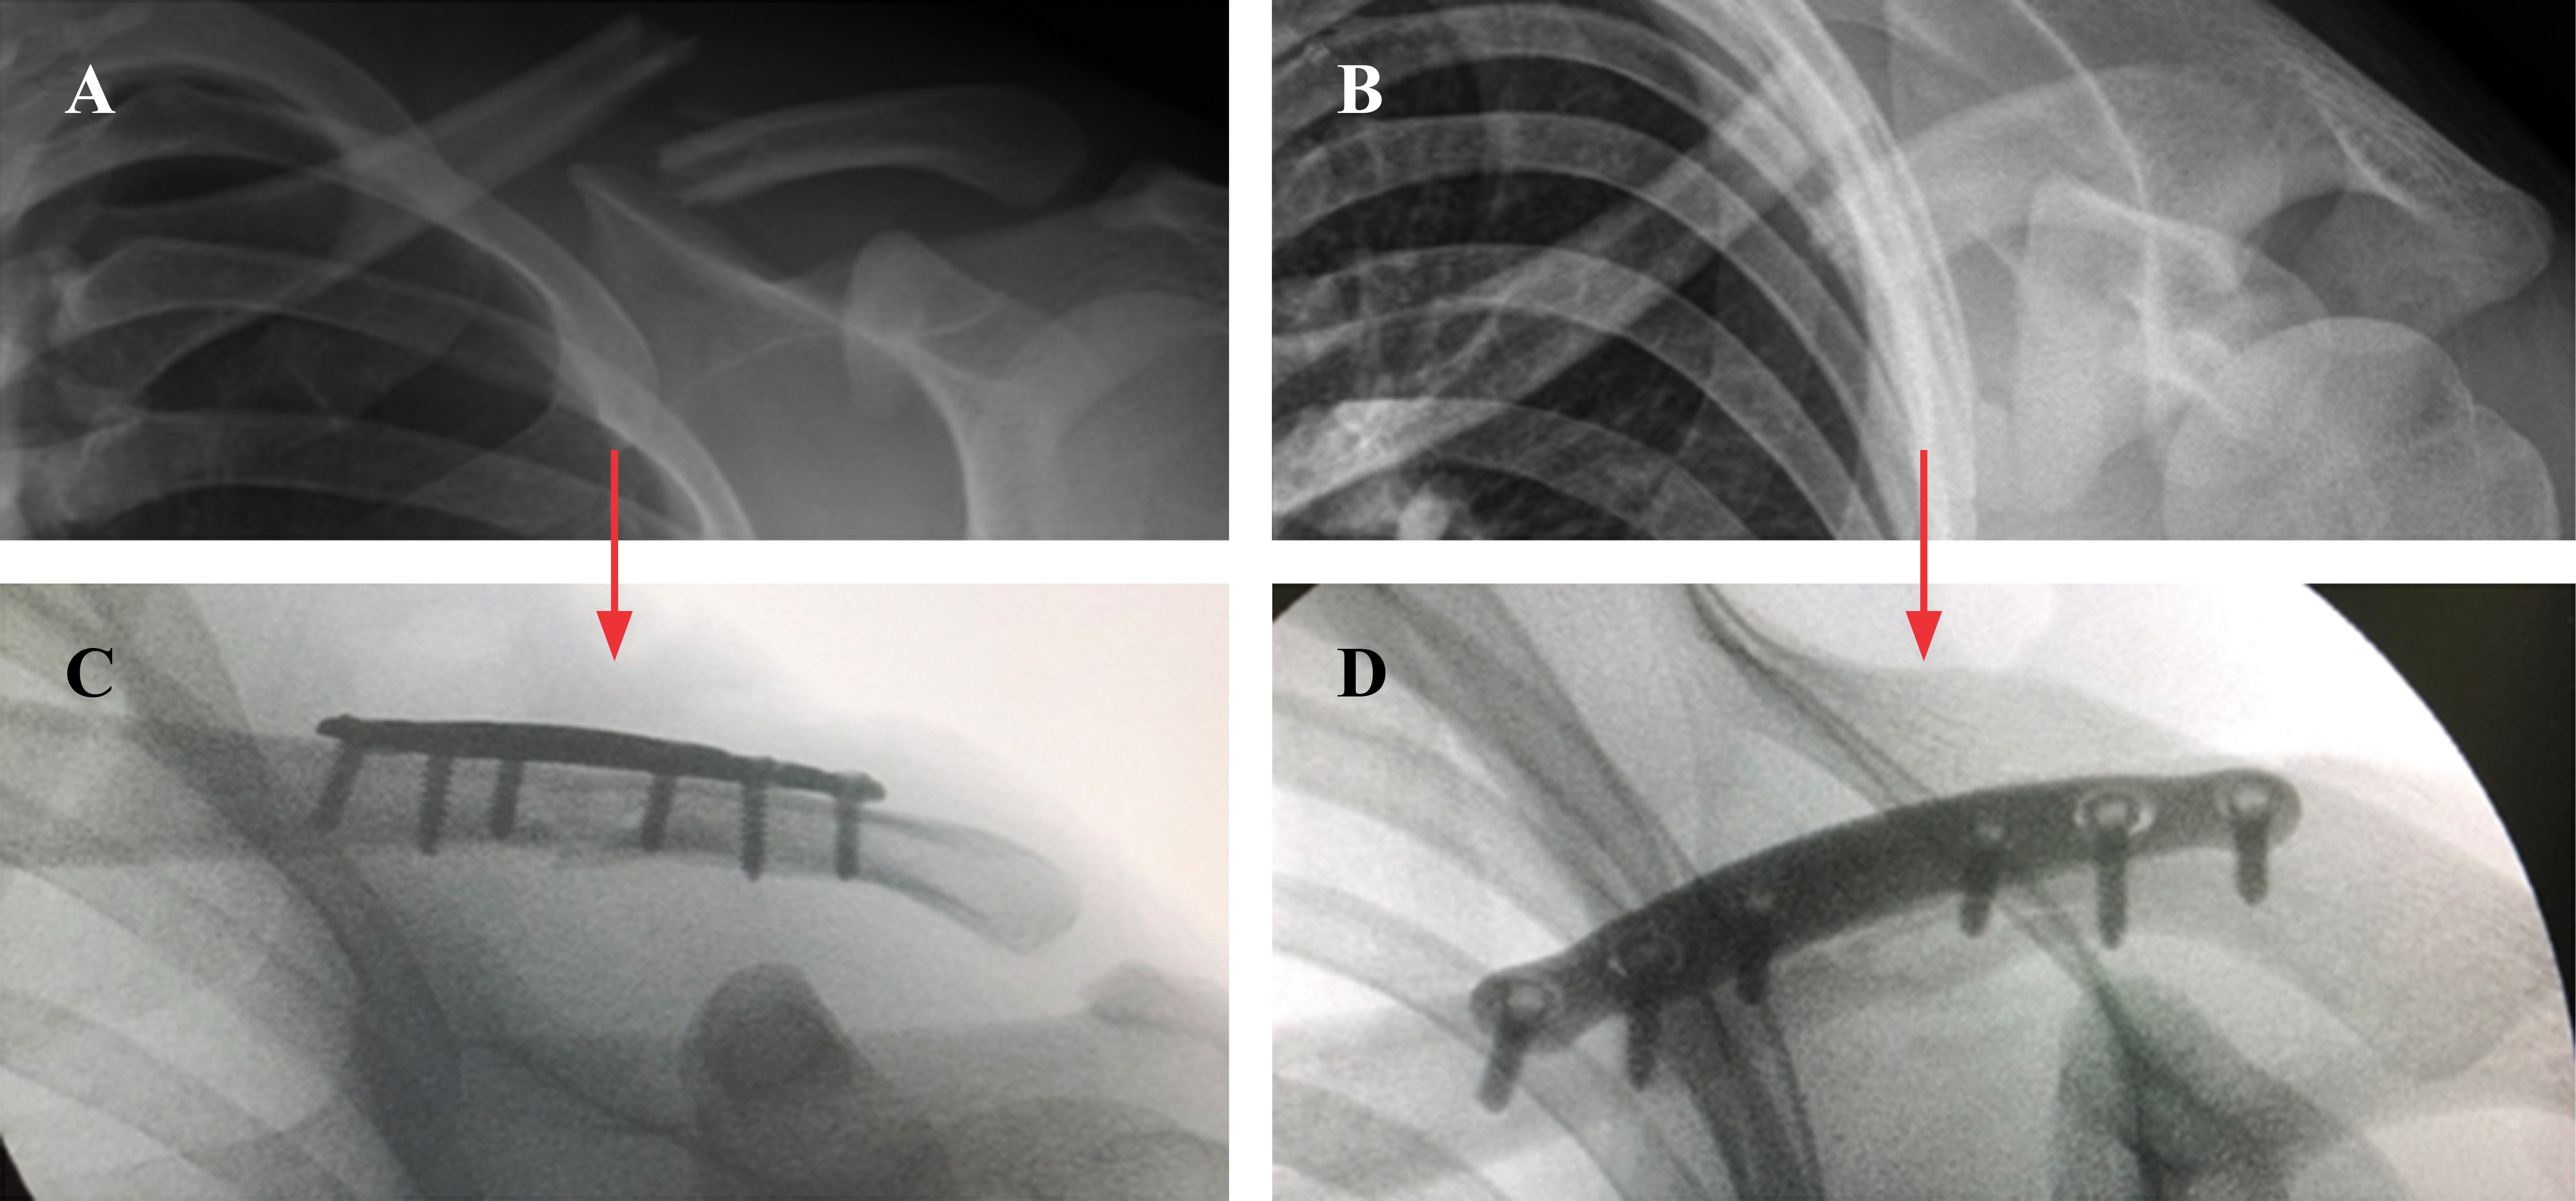

Posteriormente se realizan las respectivas incisiones cutáneas, respetando la piel sobre el foco de fractura y disecando con electrobisturí hasta el plano óseo (Figura 3A). Con ayuda de un desperiostizador se efectúa un estuche perióstico alrededor de cada fragmento óseo y un túnel submuscular entre ambos, justo sobre la clavícula a nivel del foco de fractura. A través de las incisiones y con ayuda de dos pinzas de reducción se realiza una reducción instrumentada de la fractura (Figura 3B y C). En este punto es posible efectuar una fijación transitoria para ayudar a mantener la reducción mediante el uso de una aguja Kirschner o una pinza de reducción tipo Backhaus. Utilizando una torre de bloqueo fija a un extremo de la placa, ésta se desliza en forma submuscular fijándola transitoriamente a ambos lados de la fractura con pinzas de reducción y/o agujas de Kirschner. Una vez obtenido un adecuado posicionamiento bajo fluoroscopía de la placa en el plano mediolateral y anteroposterior, se fija definitivamente el fragmento proximal y luego el distal con un tornillo bicortical no bloqueado central a cada lado de la fractura, para luego bloquear el constructo mediante la colocación de un tornillo de bloqueo a cada lado de los tornillos corticales (Figura 3D-F). En la Figura 4 se esquematiza una configuración de tornillos recomendable para este tipo de fracturas. Una vez completada la fijación con tornillos se comprueba que exista una adecuada reducción de la fractura así como un satisfactorio posicionamiento de la placa y largo de los tornillos en al menos dos planos ortogonales entre sí (Figura 5). Por último, se procede al cierre del plano muscular y subdérmico, utilizando suturas cutáneas reforzadas para la piel (Steri-Strip™; 3M®) más una cobertura con dos apósitos impermeables transparentes (Opsite™; Smith and Nephew®) (Figura 6).

Serie clínica: durante el período comprendido entre Mayo de 2017 y Mayo de 2018 fueron intervenidos 10 pacientes con esta técnica (siete hombres y tres mujeres). La edad promedio de la serie fue de 26.5 años al momento de la cirugía (rango, 17-41 años). Todos los pacientes presentaron una fractura tipo 2B1 de la clasificación de Robinson y fueron operados dentro de los 10 días siguientes de ocurrida la fractura. En todos los casos se utilizó una placa anatómica bloqueada de la misma compañía (Acumed, Hillsboro, OR, USA). El tiempo operatorio promedio fue de 79.4 ± 17.2 minutos (rango, de 60 a 105 minutos) y no se presentaron complicaciones intraoperatorias. El seguimiento promedio de la serie fue de 27.5 meses (rango, de 22 a 33.5 meses). Todos los pacientes obtuvieron una consolidación clínico-radiológica, con rangos completos de movilidad del hombro y reanudaron sus actividades tanto laborales como deportivas al mismo nivel que previo a la fractura. Ninguno de ellos presentó complicaciones durante su período postoperatorio ni necesidad de reoperación por ninguna causa hasta el momento del último control. Todos se mostraron muy satisfechos con respecto al resultado cosmético de su cicatriz operatoria, sin casos de cicatriz queloidea o hipertrófica y ningún paciente reportó una alteración sensitiva cutánea. No hubo casos de irritación o prominencia de la placa y por lo tanto, ningún caso requirió su retiro (Figuras 7 y 8).